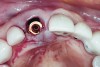

Fig 7. Occlusal view of the implant after insertion.

Figure 7

An osteotomy that used the dense cortical bone on the palatal aspect of the extraction socket was prepared, and a guide pin was inserted (Figure 5) to verify that the angulation was ideal. The implant was then inserted (Figure 6). Figure 7 shows the occlusal view of the implant in position. Note the gap between the palatally oriented implant and the buccal plate of the extraction socket.